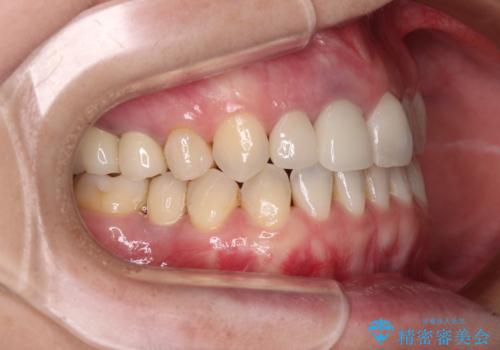

前歯のクロスバイトはインビザラインで改善し、抜歯が必要な部分はインプラントを、その他むし歯が進行している歯はセラミッククラウンによる補綴治療することとしました。

磨きにくく、何度もむし歯治療を繰り返していた前歯をスッキリと整えることができました。